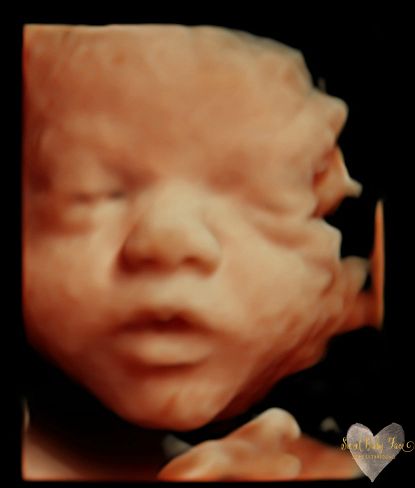

3D/4D/5D Ultrasound Gallery

Take a peek at our Photo Gallery. All of our 2D, 3D, 4D, HD elective ultrasound images are truly ours. They come directly off our machine from our highly trained staff. We can start getting great 3D/4D images as early as 10 weeks!